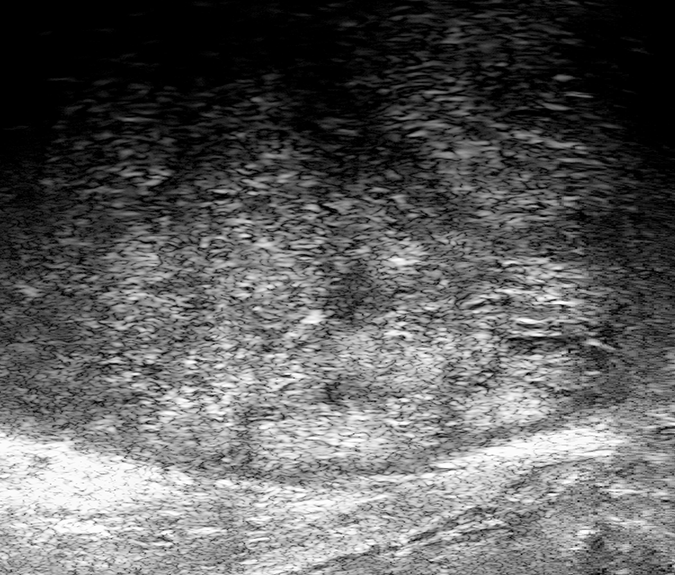

PRI-MUS 2

Hyperechoic with/without ductal patches.